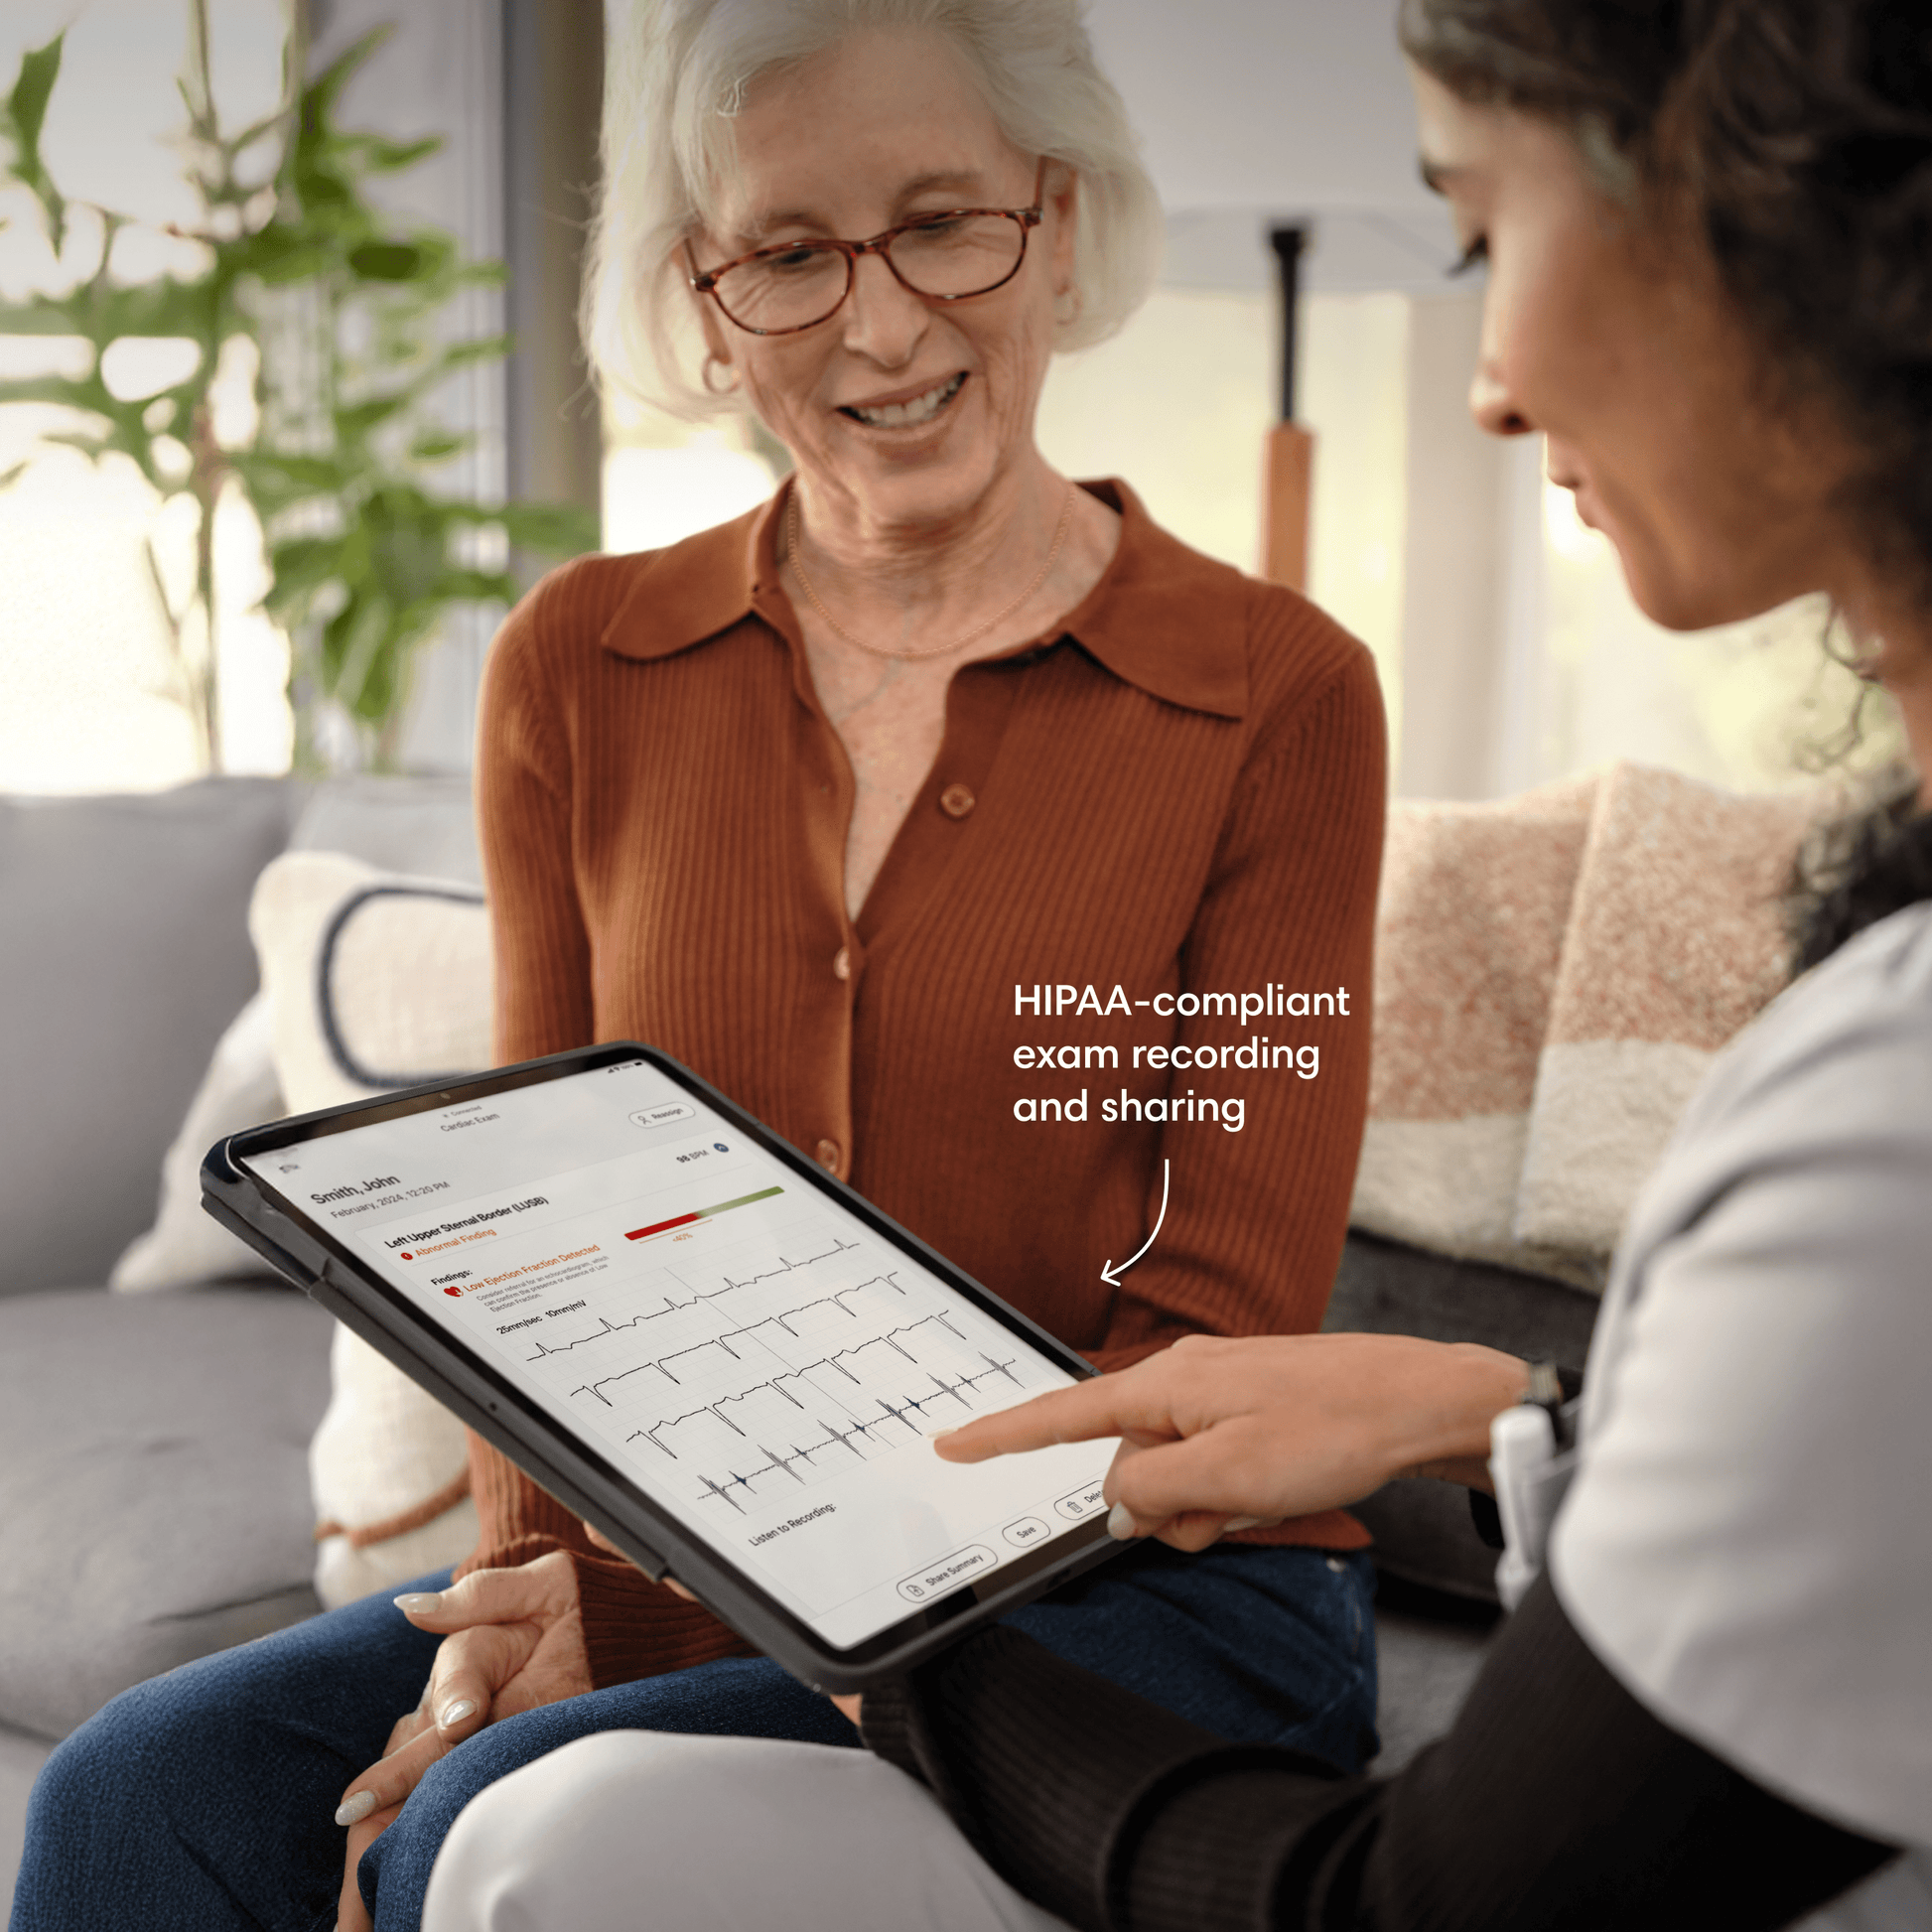

Save and share patient records.

Pair with the Eko App to save admin time, share data with colleagues, upload to your EMR, revisit past exam results, and monitor progress all while maintaining HIPAA compliance.